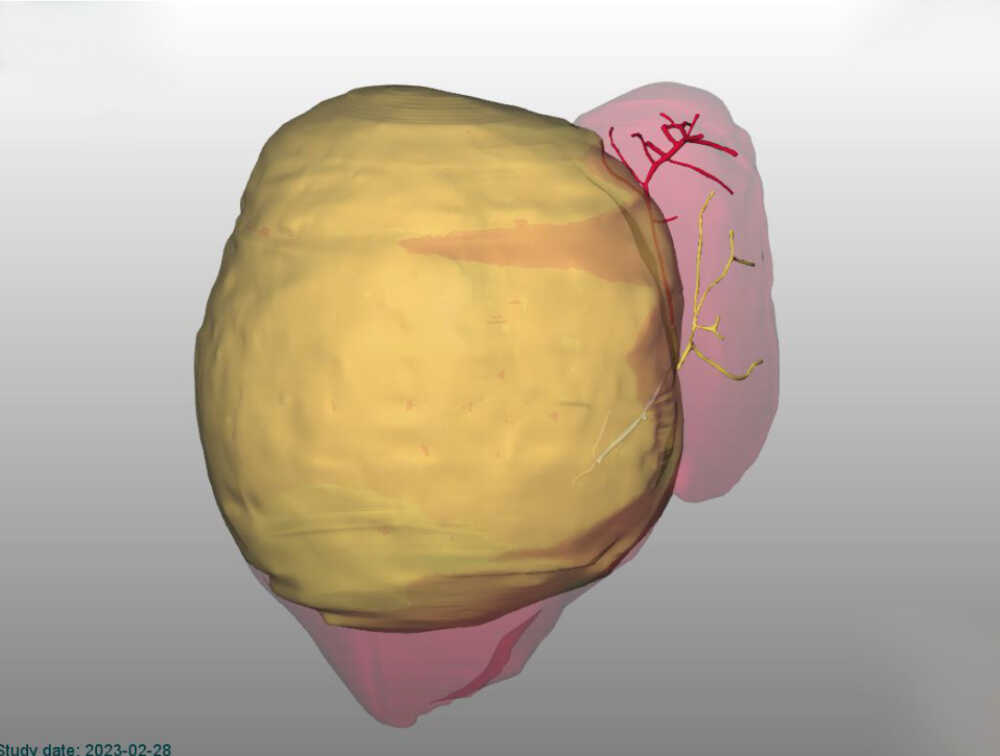

Utilizzando un sofisticato software di elaborazione delle immagini TAC è stato costruito un modello tridimensionale del fegato per valutarne le dimensioni e i rapporti del tumore con la parte sana dell’organo e i suoi vasi sanguigni. Il modello ha reso evidente che l’asportazione del tumore avrebbe lasciato una quantità insufficiente di fegato sano la quale, nonostante le capacità di rigenerazione delle cellule epatiche, non avrebbe garantito il buon funzionamento dell’organo dopo l’operazione.

A distanza di 4 settimane dall’embolizzazione portale, effettuata dai radiologi interventisti dell’Ospedale della Santa Sede, una nuova TAC con ricostruzione 3D ha confermato che il fegato sano era raddoppiato, passando da un volume stimato di 80 a 120 ml, favorendo le condizioni per effettuare l’intervento.